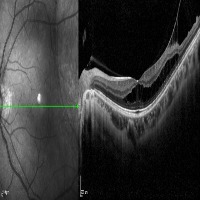

Medical Imaging Analysis: The "three-segment" model can be used by healthcare professionals for enhanced analysis of medical imaging, such as MRI or CT scans. It will help in identifying cleave classes, which can improve detection and diagnosis of potential issues in the brain, particularly those related to retina or neural connections.

Retinal Disease Diagnosis: Ophthalmologists could utilize the model to get help in diagnosing retinal diseases. It can help to identify any abnormalities by differentiating between the 'out', 'in', and 'retina' segments, enabling early detection of conditions such as retinal detachments or macular degeneration.

AI in Surgery: The model can be used to assist surgeons during complex neuro or eye surgeries. It can provide enhanced visualization, enabling real-time differentiation between various segments, leading to more precision in surgical procedures.

Medical Training and Education: The model can be used in medical learning settings, providing students with valuable visual learning material. It could serve as an advanced tool for the understanding of the retina and other segments of the brain or eye.